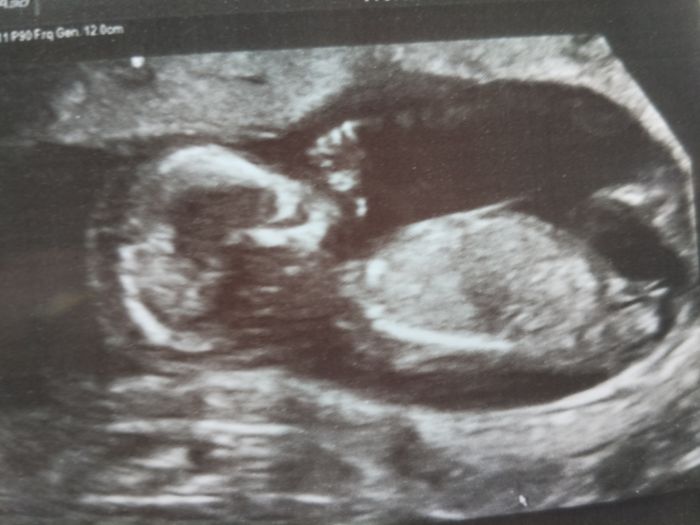

Ahoj, tak se po dlouhe dobe hlasim. Chodim do prace a je to mazec. Dneska jsem byla na screnningu a super. Taky se me ptala na pohlavi, my to vedet nechcem, mame doma kluka i holku a obleceni po nich :). Rizika gen. vad jsou mala, nechala jsem ten papir v aute a uz se mi tam nechce.  Jsem hrozne rada, ze mimco je v poradku. Jen je o neco vetsi , takze nam termin soupla na 4.9., podle MS 9.9.

Tak se hlásím z poradny. Prtě už má 7,5cm, zase spalo takže žádné skákáni v břišku jako máte všechny jsem zase neviděla... Vyšetení taky v pořádku, jen hemoglobin mám nižší a tlak hraniční. Tak mám za úkol si ho hlídat a kdyby se zvyšoval tak hned přijít...

Dnešní fotečka... :-)